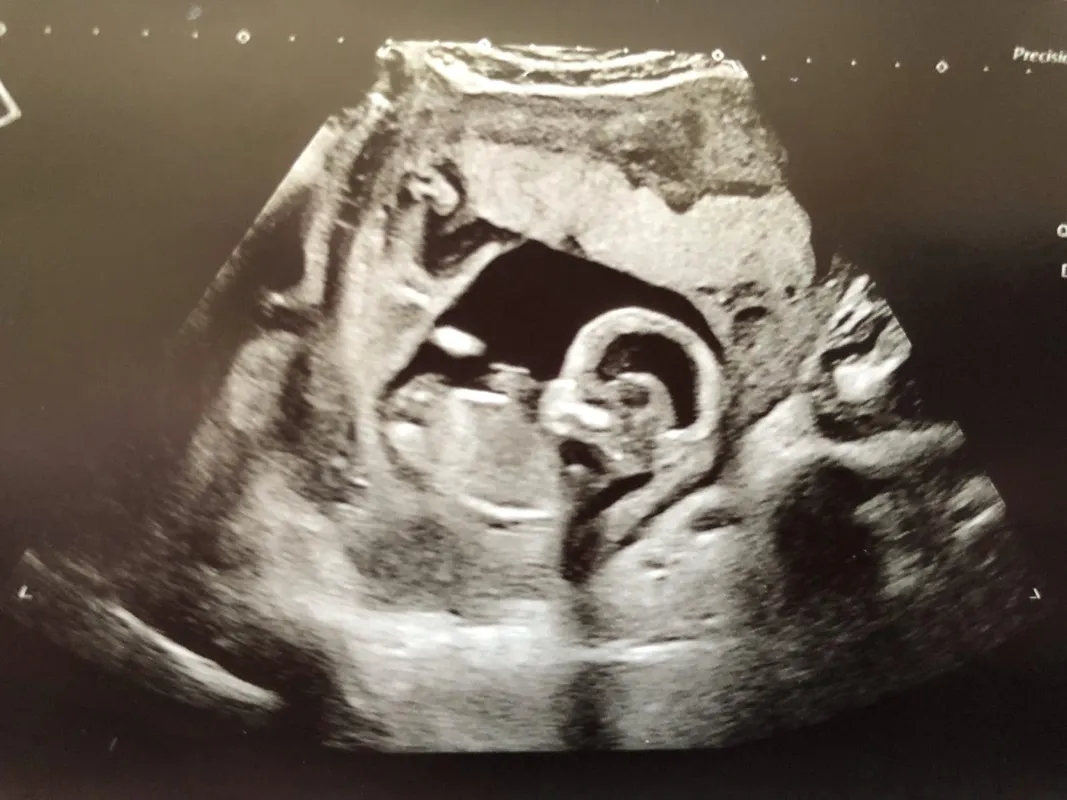

Jasmin Shattock várandóssága közben kapta a sokkoló diagnózist, miszerint kisfia, akit a szíve alatt hord, agy nélkül, illetve annak jelentős hiányával fog megszületni.

Egy rendkívül ritka betegség miatt a kicsi Barney szürkeállománya nem fejlődött ki rendesen, ami már az ultrahangon is látszott.

Jasmin Shattock sokkot kapott az ultrahangon elhangzott diagnózistól (Fotó: Northfoto)